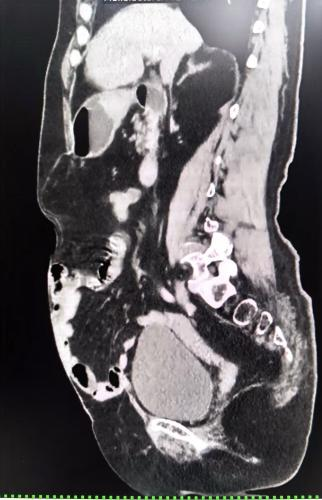

CT显示巨大腹壁缺损

就在林奶奶快要放弃时,当地医院推荐她到北京中医医院普外/肿瘤外科试一试。抱着最后一丝希望,林奶奶找到了副主任医师叶晋生。叶晋生查阅病历与CT影像后发现,林奶奶不只是简单的腹壁疝,而是切口疝合并造瘘口旁疝,再加上之前做过肠癌手术,腹腔里很可能有粘连,他耐心地向林奶奶解释病情并告诉她可以通过手术解决,不仅能把疝修补好,还能把造口还纳回去,重新恢复正常排便。这让濒临绝望的林奶奶重新看到了希望。